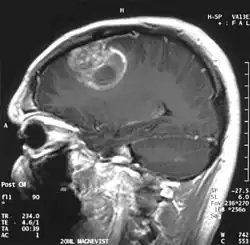

| A coronal view (from the back of the head) of a contrast-enhanced MRI revealing a glioblastoma in a 15-year-old boy | |

When viewed with MRI, glioblastomas often appear as ring-enhancing lesions. The appearance is not specific, however, as other lesions such as abscess, metastasis, tumefactive multiple sclerosis, and other entities may have a similar appearance.[61] Definitive diagnosis of a suspected GBM on CT or MRI requires a stereotactic biopsy or a craniotomy with tumor resection and pathologic confirmation. Because the tumor grade is based upon the most malignant portion of the tumor, biopsy or subtotal tumor resection can result in undergrading of the lesion. Imaging of tumor blood flow using perfusion MRI and measuring tumor metabolite concentration with MR spectroscopy may add diagnostic value to standard MRI in select cases by showing increased relative cerebral blood volume and increased choline peak, respectively, but pathology remains the gold standard for diagnosis and molecular characterization.